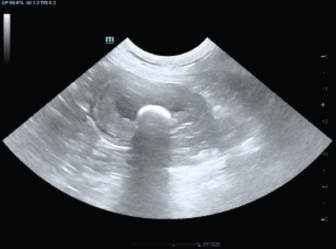

On clinical examination, the patient was alert and cooperative, with a body condition score of 5/9. Frequent attempts to urinate were observed, accompanied by signs of discomfort. Abdominal palpation revealed a tense and distended bladder. Radiography revealed no significant findings, while abdominal ultrasonography (Fig. 1) revealed a moderately distended bladder containing a hyperechoic urolith, sediment, and a thickened bladder wall. Hepatomegaly was detected with a hyperechoic lesion on the left medial liver lobe, alongside echogenic gallbladder sludge (Fig. 2). All other abdominal organs were normal. Hematology revealed lymphopenia (0.97 × 10^9/l), and biochemical analysis showed hypophosphatemia (0.70 mmol/l) and elevated liver enzyme levels (ALKP 266 U/l, GGT 22 U/l). Other parameters were within normal limits.

Fig. 2. Ultrasonographic image of the liver lobe showing a hyperechoic lesion (CCHCC) measuring 2.00 × 2.05 cm.